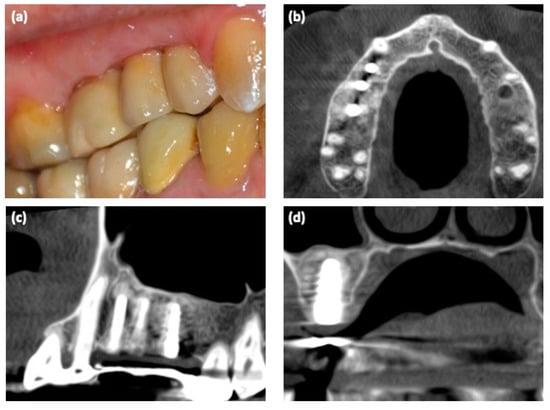

The dental X-ray showed the presence of a large cystic lesion related to teeth #14–16, which previously had been endodontically treated (Figure 1a). Thus, to evaluate the 3D dimensions of the lesion, cone-beam computed tomography (CBCT) with a multiplanar reconstruction program was used. The CBCT showed a periapical lesion of approximately 20 × 15 × 14 mm, with a soft, fluctuant, and cystic consistency, resulting in a critical-size alveolar bone defect [1,10] (Figure 1b–d).

Figure 1. Radiological examinations. (a) Detail of the dental X-ray at the first clinical examination; (bd) 3D CBCT scan before surgery.